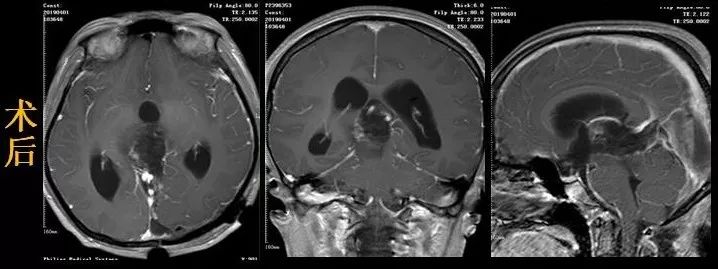

专家们经过反复的术前讨论和精心准备,由樊友武主任主刀为刘女士实施手术,手术采用改良POPPEN入路,牵开左侧枕叶,切开小脑幕显露肿瘤,然后小心避开大脑大静脉及大脑内静脉,在脑干背侧仔细辨认肿瘤界限,分块切除。持续近两个小时在显微镜下操作的手术,终于将肿瘤完全切除。

病理切片结果确诊为毛细胞型星型细胞瘤,属于低级别胶质瘤。随后专家充分利用手术切口,经侧脑室枕角穿刺,将分流管绕过中脑导水管的梗阻部位,另一端向下放入枕大池,等于重建了脑脊液的循环通路,同期解决了梗阻性脑积水的问题。

因为发现及时,经过手术完全切除病灶后,结合脑胶质瘤诊疗规范(2018年版),刘女士属于年龄40岁以下,肿瘤完全切除的情况,符合低危因素,可以随访定期复查,不需要后续放化疗。术后刘女士恢复顺利,术前症状改善,肢体活动正常,目前已经痊愈出院。